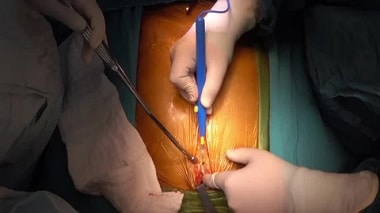

Cómo Se Hace Una Cirugía Cardíaca

Para realizar las cirugías de corazón abierto generalmente el cirujano cumple con las siguientes pautas:

- Deberá evaluar exhaustivamente los riesgos que puede tener la operación para la vida del paciente, saldado este paso el paciente entra a quirófano y es anestesiado completamente.

- Luego se procede a abrir el esternón del paciente para exponer al corazón

- Posteriormente, se conecta el paciente a la máquina que hará la función de oxigenación de la sangre que recorre todo el cuerpo.

- Estando el corazón disponible se procede a corregir el problema cardiaco que presente el paciente.

- Una vez resuelto se cierra el esternón con sutura de acero.

En intervenciones no invasivas los galenos colocan al paciente en anestesia y proceden a practicar la pequeña incisión donde se introduce el material tecnológico para hacer el trabajo operatorio.